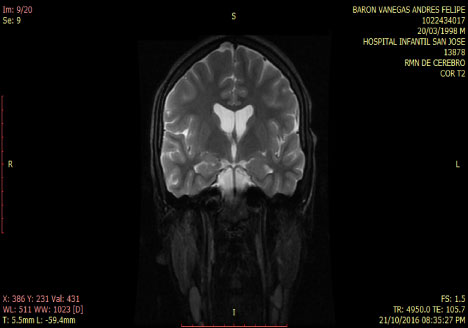

Smoker of marijuana onset 14-years-old. In the neurological and psychiatric exam is observed with commitment in sensoperception thought, glabellar and hoffman's signs. The lab test was normal MRI and tracotography were done (Figure 1 and Figure 2).

Figure 1: T2 Coronal MRI: normal. View Figure 1